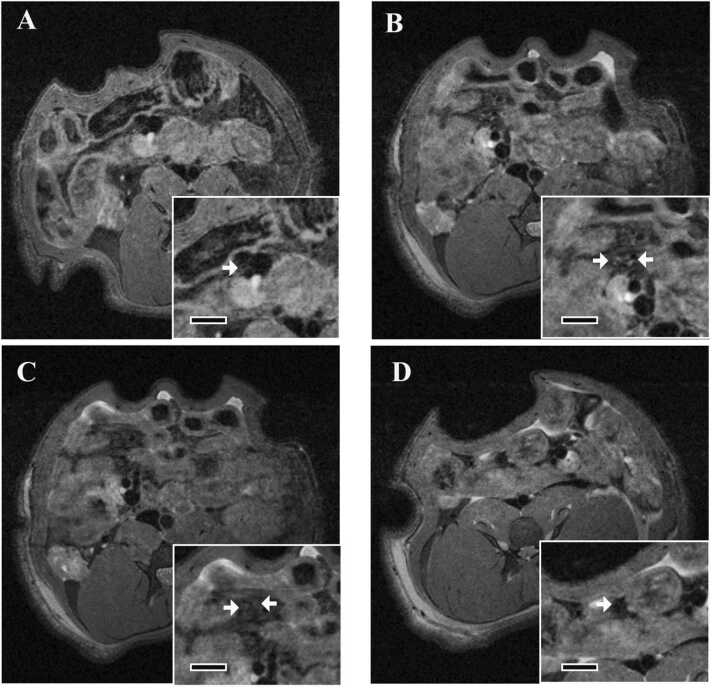

Fig. 1.

Representative histopathological images of affected lesions of the mesenteric, pancreatic, gastrointestinal, and renal arteries stained with hematoxylin and eosin from the study to find MH dose and evaluate the details of MH-induced arteritis. Edema, infiltration of inflammatory cells, and proliferation of fibroblasts were observed in the perivascular area. (A-D) Histopathological images of the arteries after MH administration. (A) Mesenteric artery; Bar, 70 µm. (B) Pancreatic artery; Bar, 100 µm. (C) Gastrointestinal artery; Bar, 70 µm. (D) Renal artery; Bar, 100 µm. Perivascular edema is indicated with asterisks.

In all groups, minimal to mild perivascular infiltration of inflammatory cells, proliferation of fibroblasts, and edema were observed in the mesenteric arteries. These changes were also observed in the pancreatic arteries, gastrointestinal arteries, and renal arteries in the group 4 (25 mg/kg/day subcutaneously for 2 days; minimal to mild). In addition, these changes were observed in the pancreatic arteries of the group 3 (50 mg/kg/day orally for 4 days; minimal), gastrointestinal arteries of the group 2 (50 mg/kg/day orally for 2 days; minimal) and renal arteries of the group 1 (25 mg/kg/day orally for 2 days; minimal). In regard to the gastrointestinal arteries, these lesions were mainly observed in arteries in serosa and adipose tissue around the gastrointestinal tract. On the other hand, no abnormality was observed in the femoral arteries and arteries in the heart including the coronary arteries in all groups.

Perivascular infiltration of inflammatory cell, proliferation of fibroblasts, and edema were observed in the mesenteric arteries of 2 of 3 animals in the group 1 (25 mg/kg/day orally for 2 days; minimal), 2 of 2 animals in the group 2 (50 mg/kg/day orally for 2 days; minimal to mild), 2 of 2 animals in the group 3 (50 mg/kg/day orally for 4 days; minimal), 3 of 3 animals in the group 4 (25 mg/kg/day subcutaneously for 2 days; minimal to mild), and 1 of 3 animals in the group 5 (40 mg/kg/day subcutaneously for 4 days; minimal). Details of the histopathology of samples from the study to find MH dose and evaluate the details of MH-induced arteritis are shown in Table 2 and the lesions observed in these arteries are shown in Fig. 1.